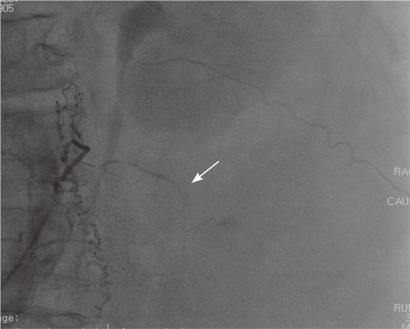

Spontaneous retroperitoneal hemorrhage is a distinct clinical entity that can present in the absence of specific underlying pathology or trauma and is typically associated with anticoagulation therapy. We report a case of a 74-year-old female patient with a cerebral infarction related to atrial fibrillation who developed a spontaneous lumbar arterial hemorrhage complicating heparin therapy. The diagnosis was suggested by a computed tomography scan and confirmed by angiography. She was treated successfully with transcatheter embolization.

自发性腹膜后出血是一种明显的临床实体,可在无特定潜在病理或创伤的情况下出现,通常与抗凝治疗有关。我们报告了一例 74 岁女性患者,因心房颤动相关脑梗死,在接受肝素治疗时发生自发性腰动脉出血。计算机断层扫描提示诊断,血管造影证实。她成功接受了经导管栓塞治疗。